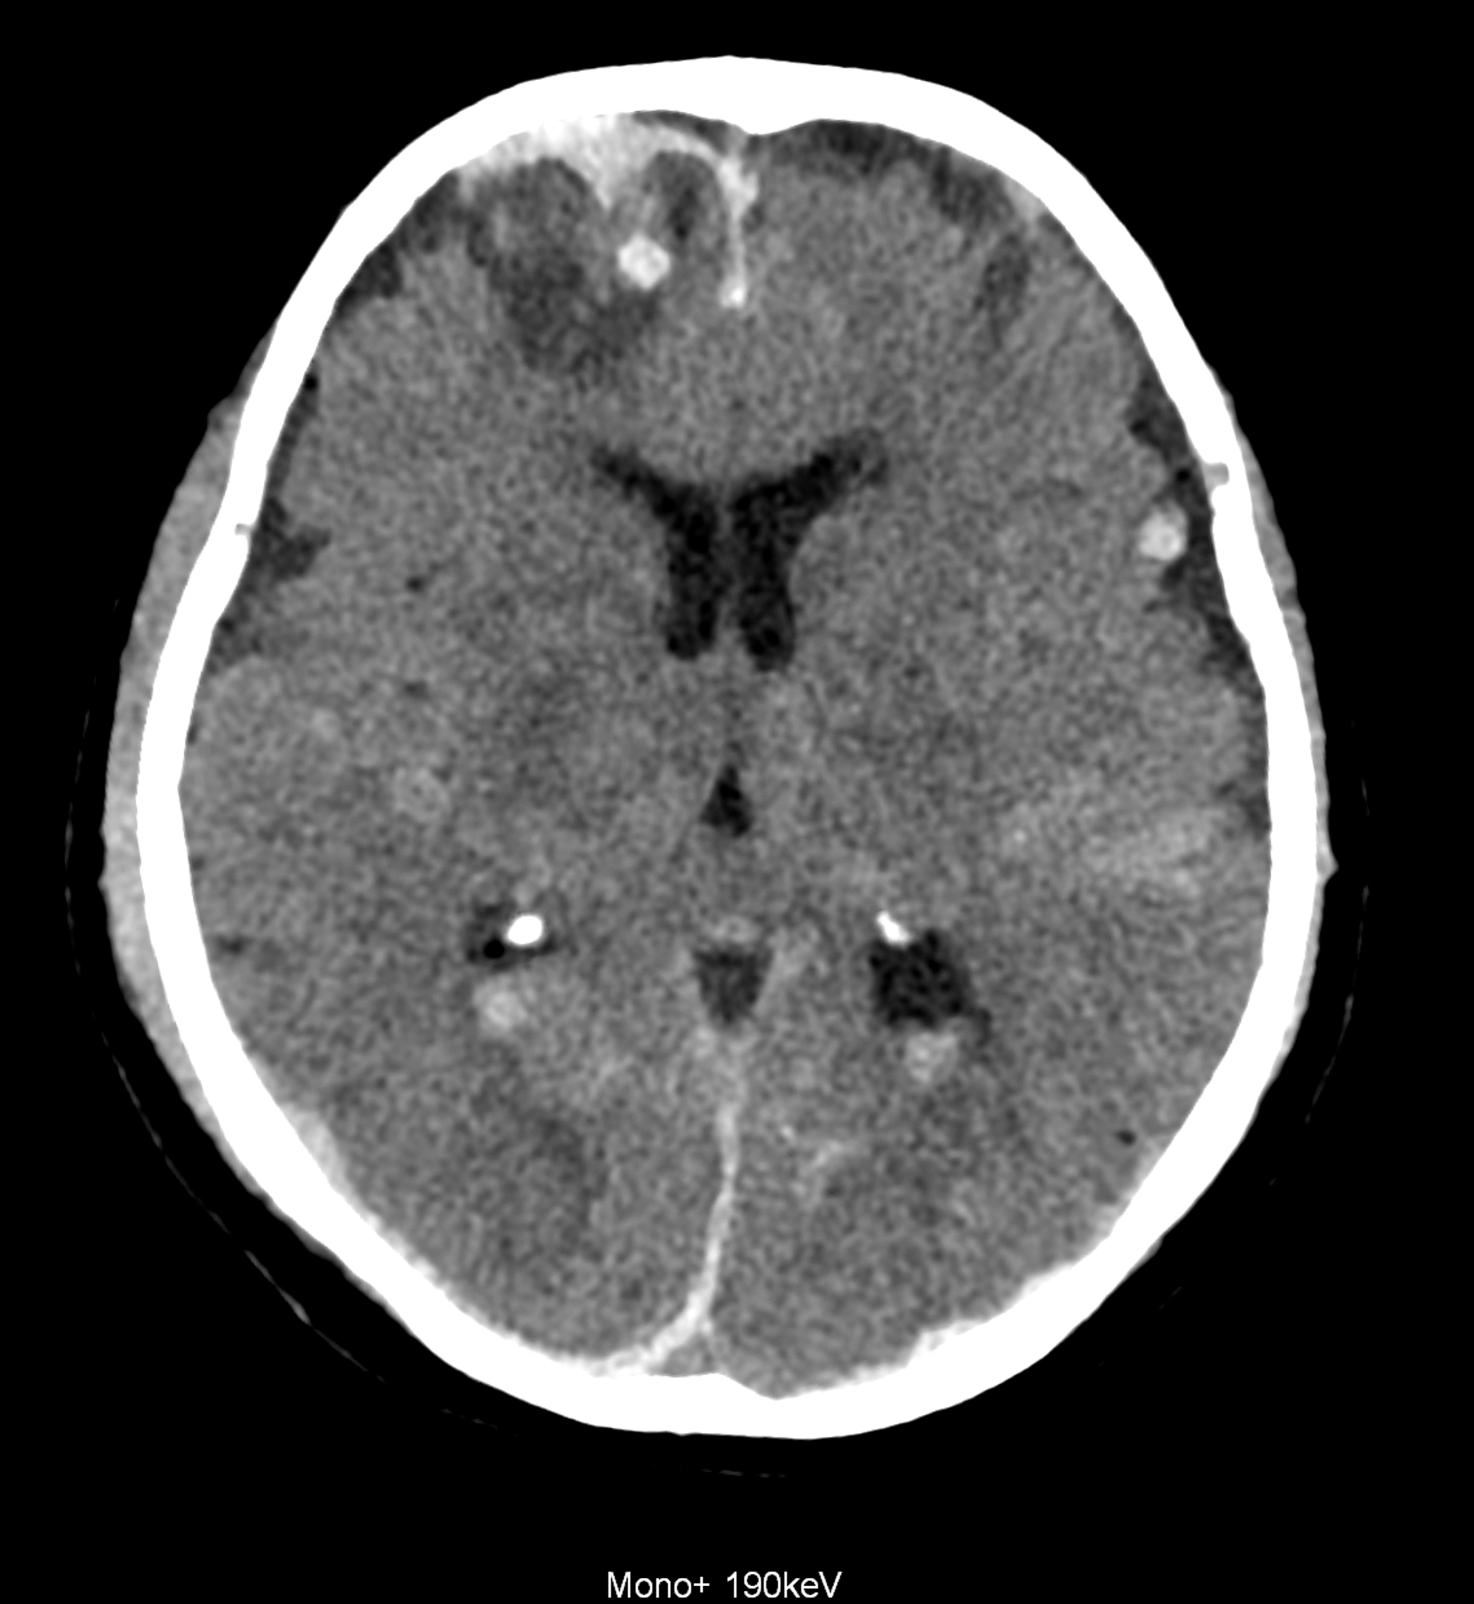

Bleeding is characterized by different absorption characteristics than healthy brain tissue (both gray and white matter) and cerebrospinal fluid. Due to the higher proportion of proteins with amino acids with disulfide bonds, the signal intensity increases at higher energies, making it possible to use monoenergetic imaging at energies above 140 keV, and/or virtual non-contrast. The hemorrhage then becomes more hyperdense, while the rest of the brain tissue acquires a uniform low signal. In addition to bleeding, areas of extracellular fluid of vasogenic origin are also imaged, i.e., in areas around contusion-type brain tissue injuries.

An example of the use of spectral imaging in complex brain injury, where contusions, diffuse axonal injury, subarachnoid hemorrhage, subdural hemorrhage, and blood in the ventricular system are present.

comparison of the images with the energies of monoenergetic reconstructions 40 keV, 67 keV (standard conventional reconstruction), 190 keV and virtual non contrast (VNC)